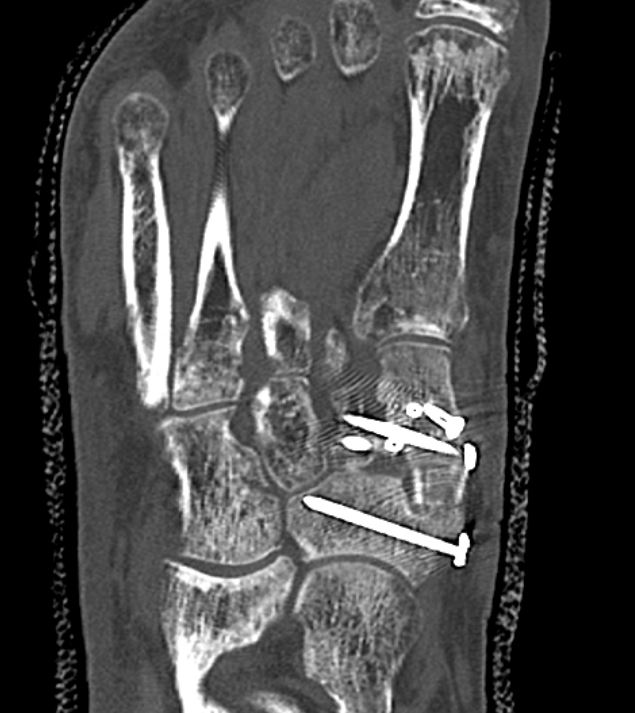

CT transversal komplexe Mittelfußarthrodes mit Spaninterposition MK